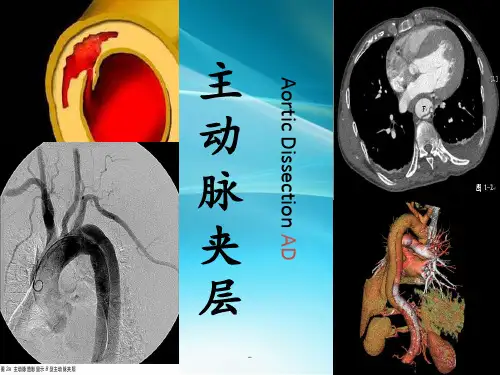

主动脉夹层(AD)

主动脉夹层(aortic dissection, AD)是起病急骤、进展迅 速、 病死率高的急性主动脉疾病。AD始发于主动脉内膜和中层撕裂形成内膜 撕裂口, 使中层直接暴露于管腔, 主动脉腔内血液在脉压的驱动下, 经 内膜撕裂口直接穿透病变至中层, 将中层分离并形成夹层。